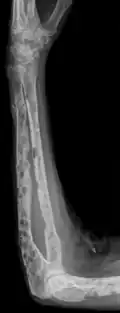

X-ray of the forearm, with lytic lesions -

The diagnostic examination of a person with suspected multiple myeloma typically includes a skeletal survey. This is a series of X-rays of the skull, axial skeleton, and proximal long bones. Myeloma activity sometimes appears as "lytic lesions" (with local disappearance of normal bone due to resorption) or as "punched-out lesions" on the skull X-ray ("raindrop skull"). Lesions may also be sclerotic, which is seen as radiodense.[76] Overall, the radiodensity of myeloma is between −30 and 120 Hounsfield units (HU).[77] Magnetic resonance imaging is more sensitive than simple X-rays in the detection of lytic lesions. An MRI may supersede a skeletal survey, especially when vertebral disease is suspected. Occasionally, a CT scan is performed to measure the size of soft-tissue plasmacytomas. Nuclear Medicine Bone scans are typically not of any additional value in the workup of people with myeloma (no new bone formation; lytic lesions not well visualized on nuclear bone scan).